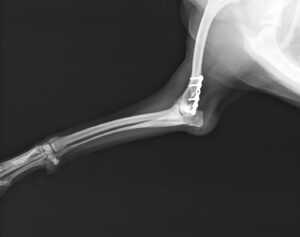

階段からころげおちてかかりつけ医を受診し、X線にて左側「上腕骨外顆骨折」を認めたため、当院の整形外科にご紹介いただきました。この症例は、尺骨の骨切り術を併用し外顆の骨折部分を整復しています。術後の経過は良好で、手術から7ヶ月後に尺骨のインプラントを除去し、治療終了としました。